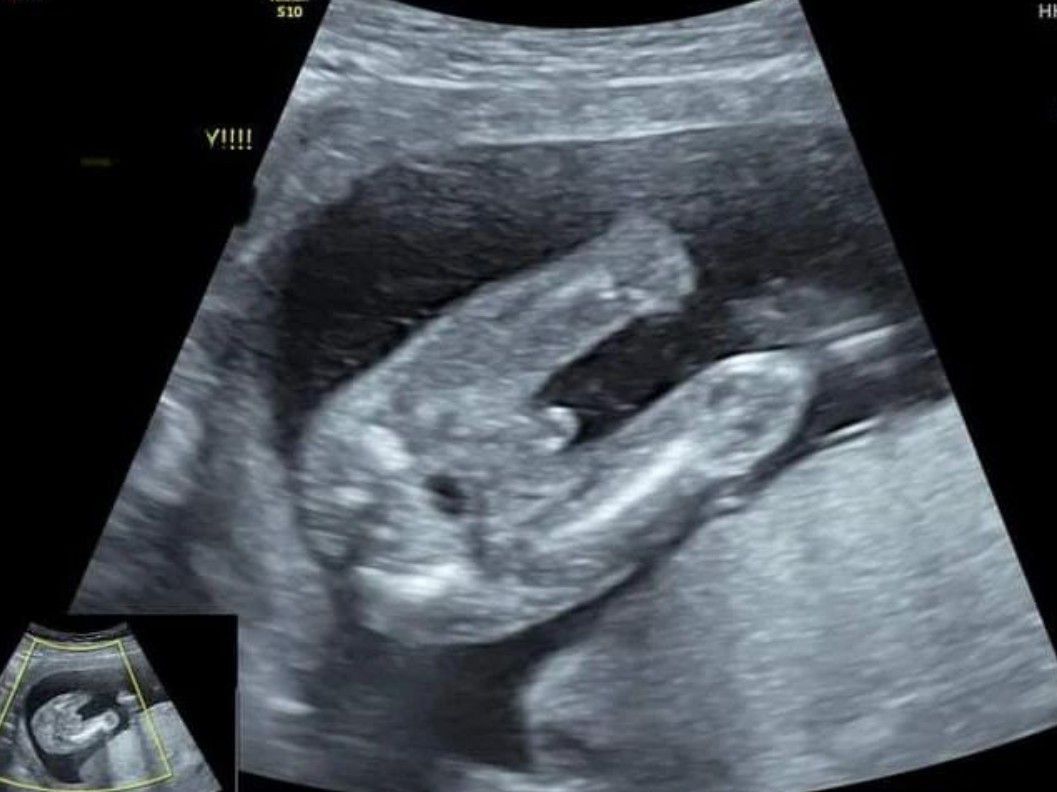

A pregnant lady presented to the clinic asking to know the gender of her baby. Ultrasound showed this. Is it a boy or a girl?